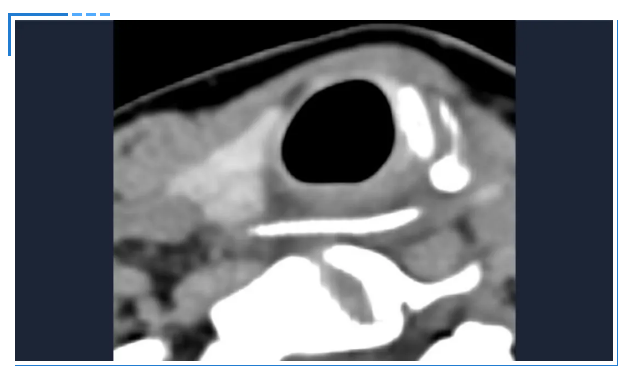

接诊的吕主任详细询问了陈女士的情况,结合她持续加重的咽痛,判断事情没那么简单。立即安排她进行双源CT检查并辅以三维重建技术。检查结果让所有人都捏了一把汗:一根近3公分长的鱼刺,深深卡在食管入口处,不仅位置刁钻,还已经刺穿食道,周围创面出现感染。